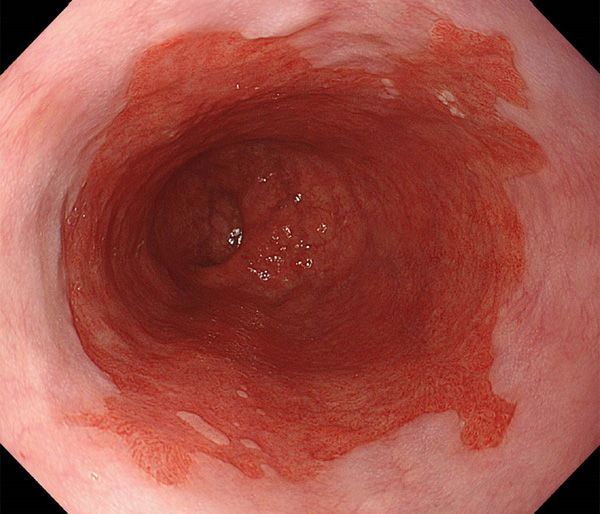

内視鏡所見と病理組織像の1対1対応が可能な症例を公募いたします。主にLSBEに発生した早期癌(HGDを含む)を対象としますが、興味深い症例であればSSBE癌でも結構です。採否は世話人へご一任ください。

特に、本邦では極めて稀なlong segment Barrett’s esophagus(LSBE)から発生した早期癌は、診断に難渋する場合も多く、欧米ではランダム生検による検出が標準的とされています。背景のBarrett食道もろとも全体を内視鏡切除+ラジオ波焼灼する欧米と異なり、ESDで内視鏡的な局所切除が基本の本邦では、存在診断+範囲診断(特に水平)を的確に行うことが不可欠です。

そのためには、一流の病理医による組織学的診断とエキスパート内視鏡医による拡大内視鏡像との一対一対応を徹底的に行うことで、『本来、見えないであろう拡大所見の先にある組織構築像が診えてくる』所まで内視鏡診断レベルを上げていく必要があります。その実現には、一対一対応を追究した症例(特にLSBE発生例)1例でも多く経験するしかありません。本研究会でBarrett食道腺癌(LSBE発生早期病変)を共に学び、拡大内視鏡像の一歩先を診るスキルを習得しましょう!一人でも多くの皆様のご参加をお待ちしています。

私は、Barrett食道癌はHGDも含め、内視鏡による存在診断、範囲診断が可能と信じて来ました。しかし最近、NBI拡大観察を併用しても側方範囲診断が不可能なLSBE症例を経験しました。診断技術を向上させるためには、多くの症例を診るしかありません。そこで、Barrett食道に造詣の深い先生方に世話人をお願いし、Barrett食道研究会を立ち上げることに致しました。全国からLSBE症例を集め、内視鏡的、組織学的診断に迫りたいと思います。皆様のご参加をお待ち致します。